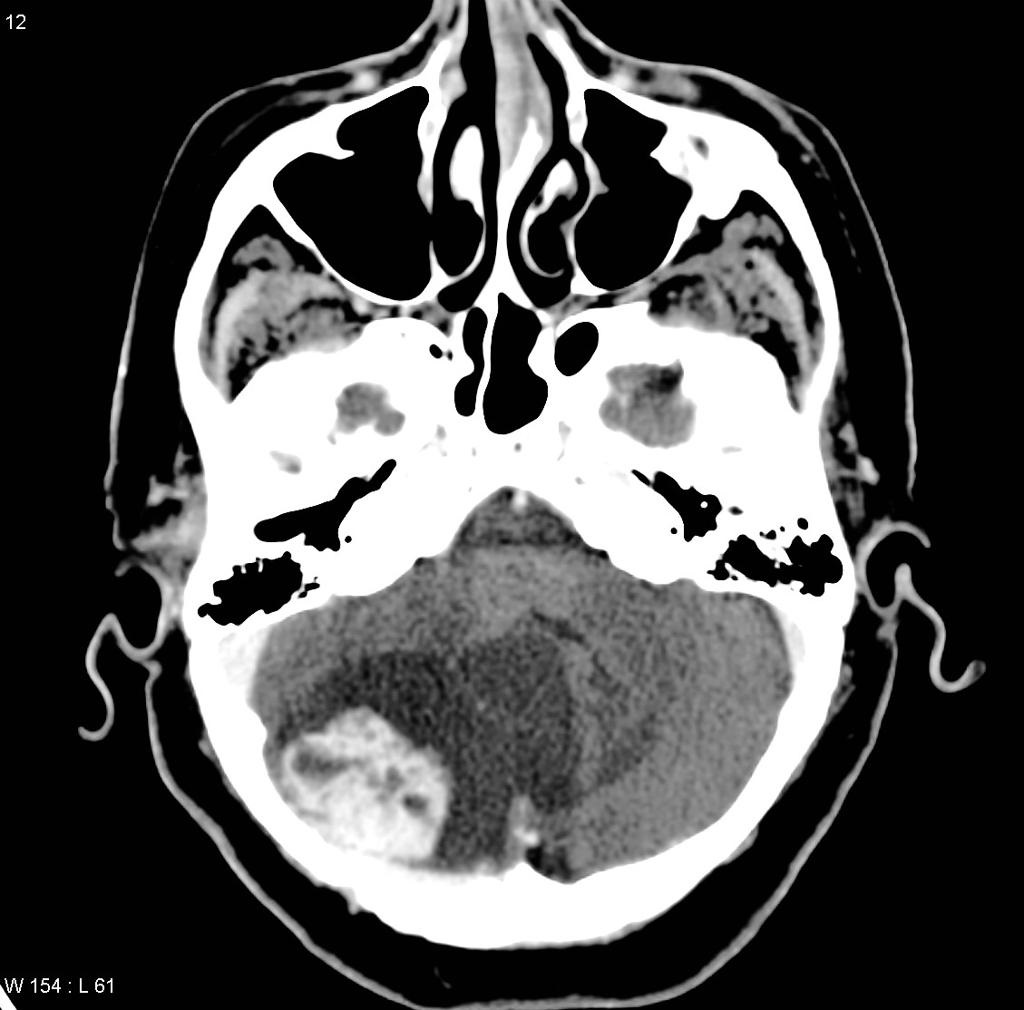

CT scan showing a cerebellar haemangioma in a patient with Von Hippel-Lindau syndrome.